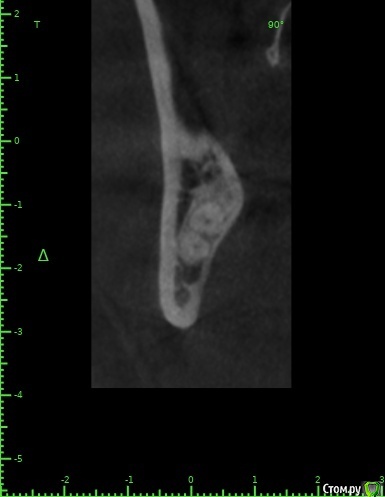

zumanok Опубликовано 15 февраля, 2021 Поделиться Опубликовано 15 февраля, 2021 Коллеги достаточно часто встречаюсь с такой картинкой на КТ в области ментального отверстия . Считаете ли вы это частью тройничного нерва или не обращать внимания? Ссылка на комментарий

Doctor Vlad Опубликовано 15 февраля, 2021 Поделиться Опубликовано 15 февраля, 2021 Коллеги достаточно часто встречаюсь с такой картинкой на КТ в области ментального отверстия . Считаете ли вы это частью тройничного нерва или не обращать внимания там что угодно может быть, больше похоже на пору кости. в этом случае до канала далеко. вы же не собираетесь так глубить? Ссылка на комментарий

zumanok Опубликовано 15 февраля, 2021 Поделиться Опубликовано 15 февраля, 2021 (изменено) там что угодно может быть, больше похоже на пору кости. в этом случае до канала далеко. вы же не собираетесь так глубить?Интересно может быть такая форма канала или стоит взять винт подлиньше? Примерно так и собирался, мб на пол мм выше. Объясните пожалуйста почему не стоит? Кроме того что коронка на 1 мм подлиньше будет. Изменено 15 февраля, 2021 пользователем zumanok Ссылка на комментарий

Doctor Vlad Опубликовано 16 февраля, 2021 Поделиться Опубликовано 16 февраля, 2021 Интересно может быть такая форма канала или стоит взять винт подлиньше? Примерно так и собирался, мб на пол мм выше. Объясните пожалуйста почему не стоит? Кроме того что коронка на 1 мм подлиньше будет.скорей всего там нерва нет и это не канал. Но. А если есть)? Ссылка на комментарий

zumanok Опубликовано 16 февраля, 2021 Поделиться Опубликовано 16 февраля, 2021 (изменено) скорей всего там нерва нет и это не канал. Но. А если есть)?Да вот,для этого и выбрал 3.5 на 8.5. Сам склоняюсь к тому что костный рисунок, информации о таком строении нерва не нашел. Думаю в процессе препарирования ложа посмотреть, если будет чувствительность то не лезть дальше.Подскажите чем Вас смутила глубина установки имплантата? Только этим образованием?По КТ 1.5мм до него. Изменено 16 февраля, 2021 пользователем zumanok Ссылка на комментарий

Raystom Опубликовано 16 февраля, 2021 Поделиться Опубликовано 16 февраля, 2021 Там будет не чувствительность, а резкий провал фрезы после определенного момента препарирования, если не отслеживать момент с глубиной, чем напугаете и себя и пациента. По поводу рисунка может быть как и костный рисунок, так и петля нижнелуночкого канала, зачем проверять? Ссылка на комментарий

Doctor Vlad Опубликовано 16 февраля, 2021 Поделиться Опубликовано 16 февраля, 2021 Да вот,для этого и выбрал 3.5 на 8.5. Сам склоняюсь к тому что костный рисунок, информации о таком строении нерва не нашел. Думаю в процессе препарирования ложа посмотреть, если будет чувствительность то не лезть дальше.Подскажите чем Вас смутила глубина установки имплантата? Только этим образованием?По КТ 1.5мм до него.как он нарисован норм, длиннее не стал бы, чтобы запас был. Просто, по вашим фото не совсем видно где канал. иногда и по кт все очень смутно. особенно когда огромные поры. Ссылка на комментарий